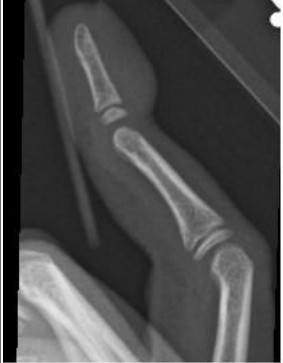

Mallet finger, or dorsal avulsion fracture, occurs when an extended DIP is forced into flexion. A typical mechanism includes a direct blow to an extended fingertip, resulting in rapid flexion with resultant increased tension on the extensor mechanism, and a dorsal distal phalanx avulsion at the attachment of the extensor tendon attachment. Clinically, this presents with dorsal tenderness with the finger held in flexion with the inability to actively extend at the DIP joint.6 Upon radiographic evaluation, volar deviation and/or a small bone fragment attached to the extensor tendon may be visible. It is important to note that a mallet finger may represent ligamentous injury alone and does not require a fracture. Patients should be treated empirically in the setting of injury with associated inability to extend the finger at the DIP joint. Prognosis is better if there is a fracture with mallet finger. Mallet injuries are generally treated acutely with splinting in extension, but they often require operative intervention if the injury is complete, with deformity or inability to extend the DIP.